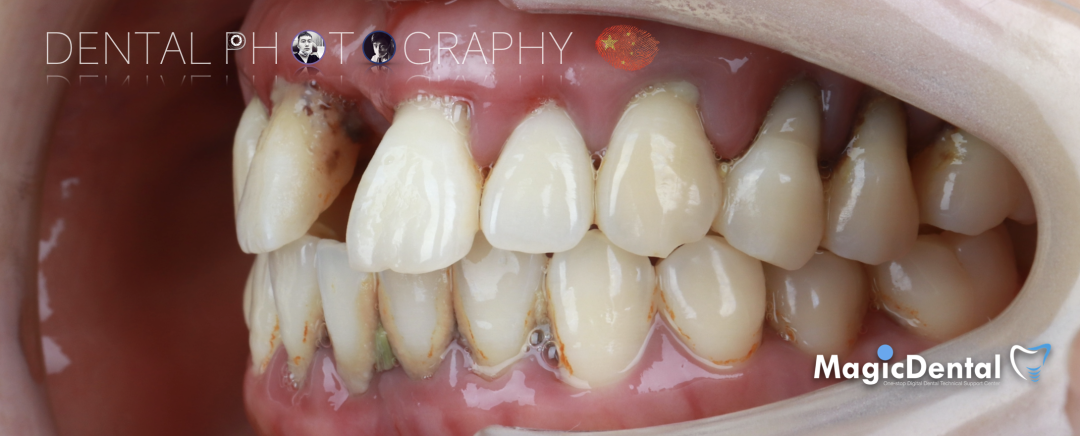

患者术前口内及面相照片

患者:32岁女性患者。

主诉:牙齿松动要求治疗。

现病史:患者两年前发现牙齿逐渐松动,近一个月左上前牙脱落,且上颌牙齿无法咀嚼,现来我院就诊要求治疗。

既往史:既往体健,无其他系统病史,否认重大疾病史,有口腔拔牙史。

口腔检查:口腔卫生差,全口牙龈红肿,牙颈部大量牙结石附着,伴有不同程度附着丧失,牙周探针深度普遍大于8mm,上颌牙列I~III°松动。

CT显示牙槽骨水平吸收严重,大多数吸收至根尖。

诊断: 全口慢性牙周炎,上颌牙列缺损。